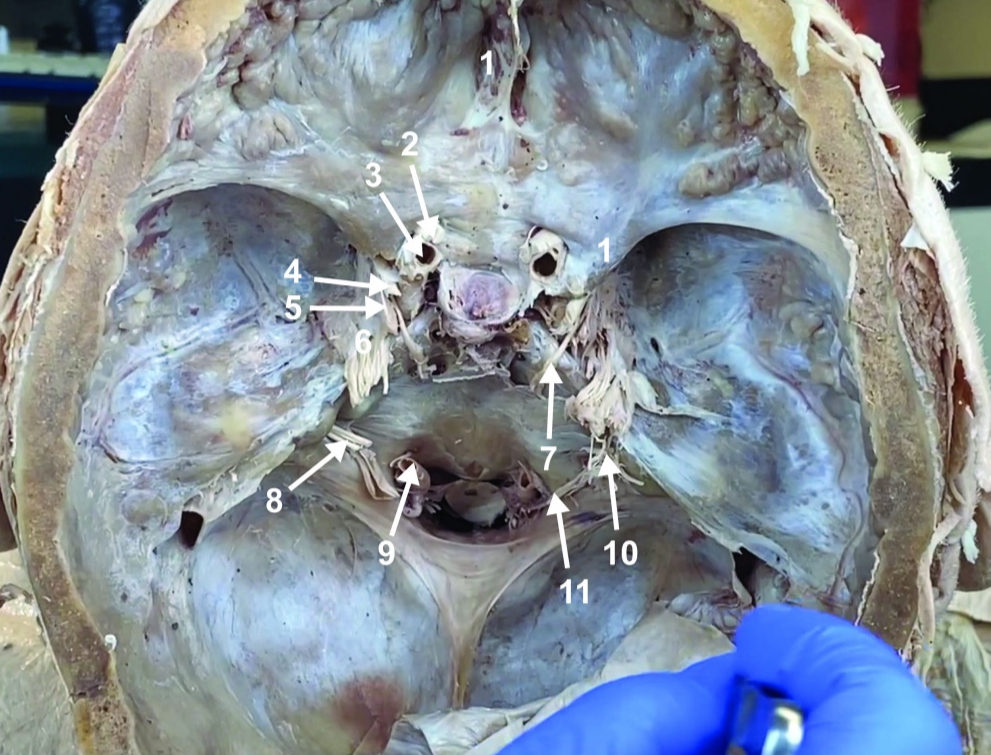

Foramen magnum

ID structure

Foramen ovale

ID structure

Foramen spinosum

ID structure

Cribiform plate

ID structure

Optic n. (CN II)

ID structure

Internal carotid a. (ICA)

ID structure

Occulomotor n. (CN III)

ID structure

Trochlear n. (CN IV)

ID structure

Trigeminal n. (CN V)

ID structure

Abducent n. (CN VI)

ID structure

Facial and vestibulocochlear n. (CN VII and VIII)

ID structure

Vertebral a.

ID structure

Glossopharyngeal and vagus n. (CN IX and X)

ID structure

Root of spinal accessory n. (root of CN XI)

ID structure

Ophthalmic division of CN V (CN V1)

ID structure

Maxillary division of CN V (CN V2)

ID structure

Mandibular division of CN V (CN V3)

ID structure

Foramen rotundum

ID structure

Foramen ovale

ID structure

Trochlear n. (CN IV)

ID structure

Abducent n. (CN VI)

ID structure